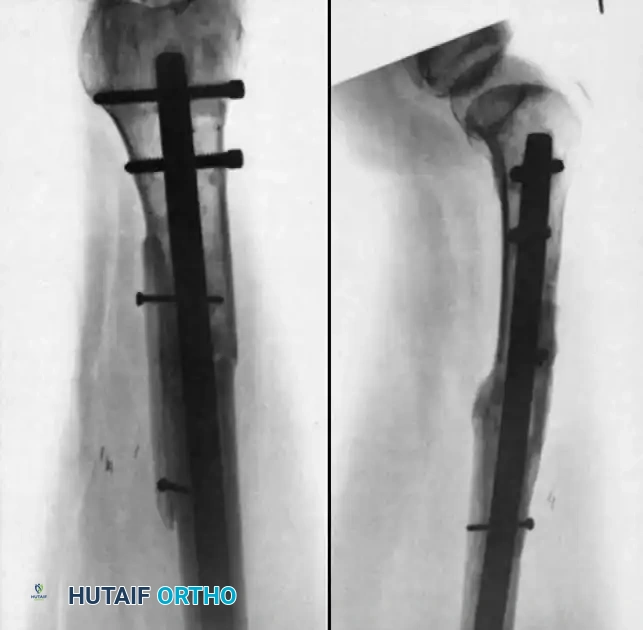

Exchange reamed intramedullary nailing is the gold standard for diaphyseal nonunions of the femur and tibia, particularly hypertrophic types.

* Indications: Aseptic diaphyseal nonunions previously treated with a smaller diameter nail, or primary treatment of diaphyseal nonunions.

* Technique:

1. Remove the existing hardware.

2. Pass a ball-tipped guide wire across the nonunion.

3. Sequentially over-ream the medullary canal. Reaming generates autologous bone graft (reamings) that is deposited at the nonunion site, while also stimulating endosteal blood flow.

4. Insert a new, larger diameter nail (typically 1-2 mm larger than the last reamer) to achieve rigid, interference fit stability.

5. Dynamization or static interlocking depends on the fracture pattern and inherent stability.

Associated Surgical & Radiographic Imaging